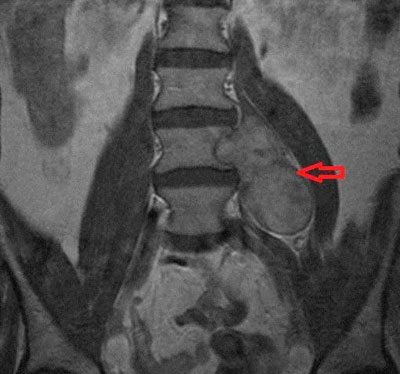

Как диагностируется рак позвоночника

После осмотра пациента, изучения анамнеза назначаются общеклинические анализы крови и мочи, гистоцитологические и цитохимические исследования. Проведение открытой (эксцизионной) или закрытой (инцизионной) биопсии позволяет установить вид опухоли, определить ее злокачественность.

В диагностике рака позвоночника используются такие инструментальные исследования:

- рентгенография;

- доплеровская ангиография;

- КТ или МРТ;

- радионуклеидное обследование;

- сцинтиграфия всего скелета.

Проведение комплексной диагностики помогает установить стадию рака, место локализации новообразования, наличие или отсутствие отдаленных метастазов.